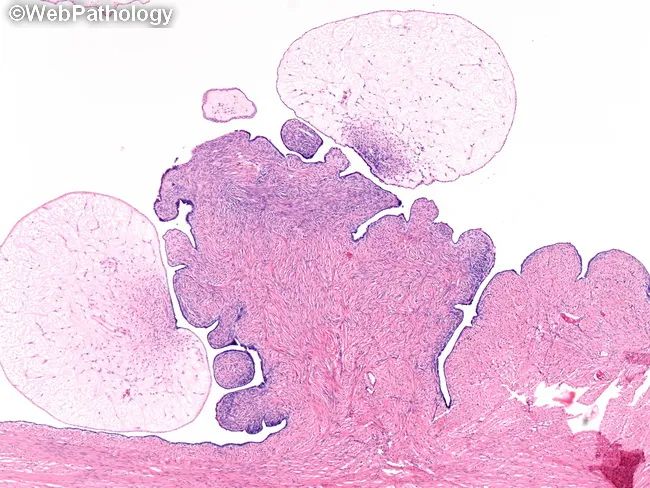

·浆液性交界性肿瘤

卵巢交界性浆液性肿瘤(Serous borderline tumour,SBT)非浸润性、低级别、浆液性上皮增生性肿瘤

多数单侧发生 (30%累及双侧,尤其是微乳头亚型)直径通常>5cm ,通常囊内生长,部分可累及卵巢表面 (腹膜种植比率更高),切面呈囊性或囊实性,囊内可见细小、易碎的乳头

(结构)囊腔内结构复杂,>10%区域衬覆上皮增生(复层、出芽和乳头)[特征] 乳头由大到小、逐级分支,并可见单个细胞或细胞团游离在腔内[特征] 局灶可能出现出芽互相融合,形成罗马桥或筛状结构,局灶可能出现微乳头型成分,范围<5mm,缺乏不规则生长的实性区、密集小巢状或复杂腺样结构 (即缺乏间质浸润)